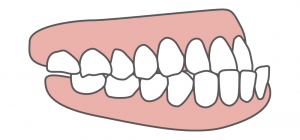

②下顎前突

下顎前突とは上顎前突の反対で下の前歯や下あごが上の歯よりも前方にでていることをいいます。

こちらも上顎前突と同様で上の前歯が後ろに傾いていたり下の前歯が前に突き出している歯自体のものと、顎のバランスが合わない骨格性のものに分かれます。

原因は上顎前突と同じになります。

下顎前突を治療する際には矯正治療+下の顎のサイズが大きい場合は外科手術を行い顎のサイズを小さくする方法もあります。